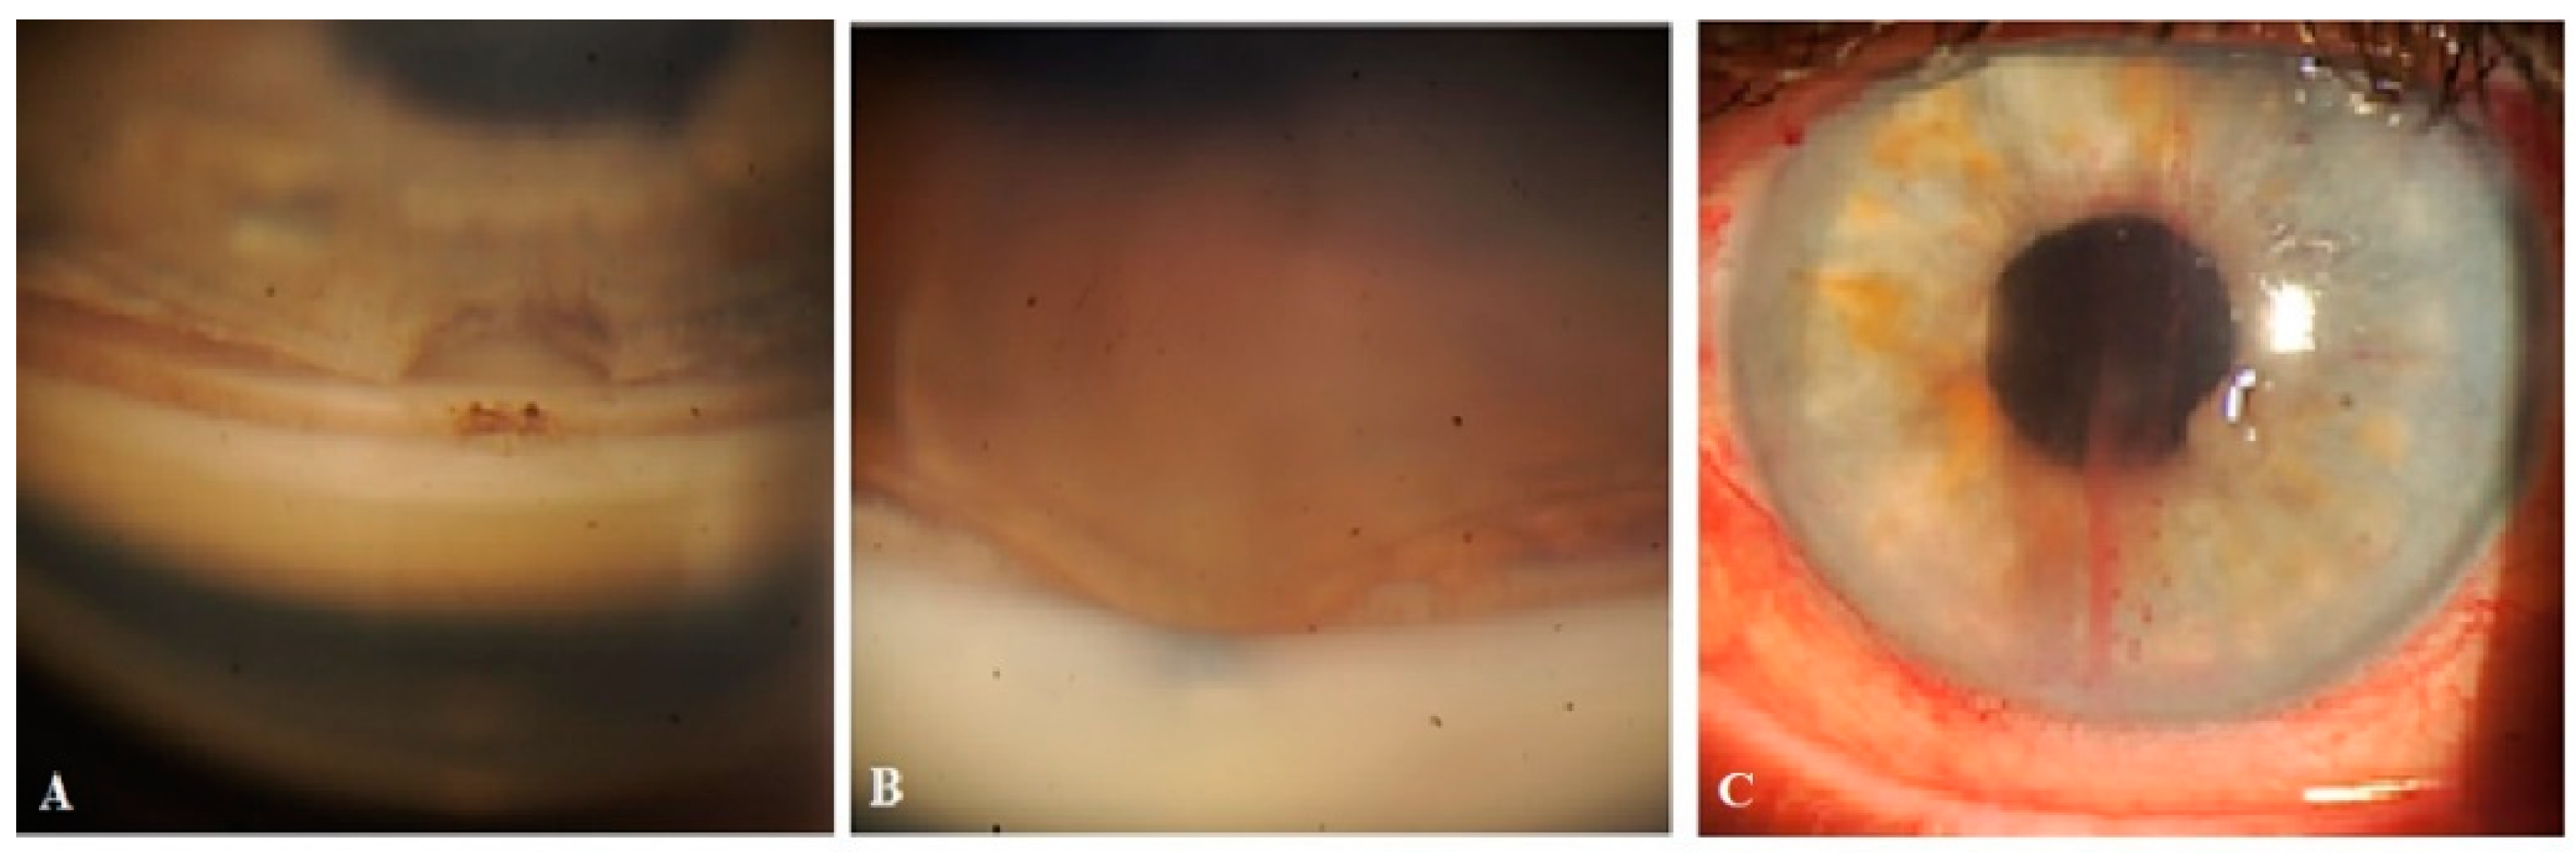

Figure 12. Case 1 (right eye): Follow-up visit at 15 months. (A) Slit-lamp view of the superior nasal quadrant showing a few CLVs, which are located far from the surgical site, and which arose directly from sclera (arrow with sky-blue border). (B) Slit-lamp image of the superior temporal quadrant and surgical site, showing the absence of blebs and CLVs (arrow with green border). (C) OCT scan of the superior nasal quadrant showing a CLV with a VLS in its lumen (white arrows); an enlarged scan of the area of interest is displayed nearby, enclosed by a red boundary. CLV = conjunctival lymphatic vessel; VLS = valve-like structure.